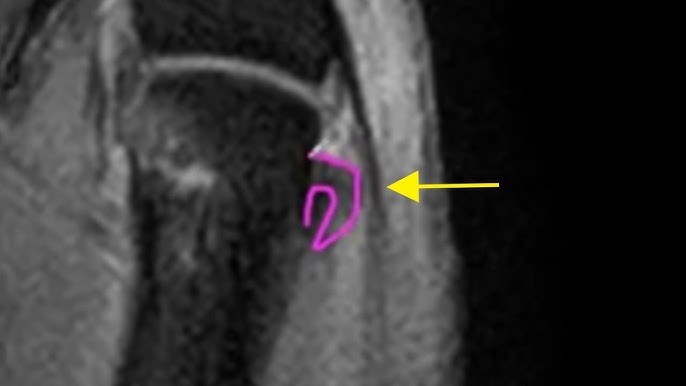

Plantar Plate Tear Radiology Reference Article Radiopaedia Org